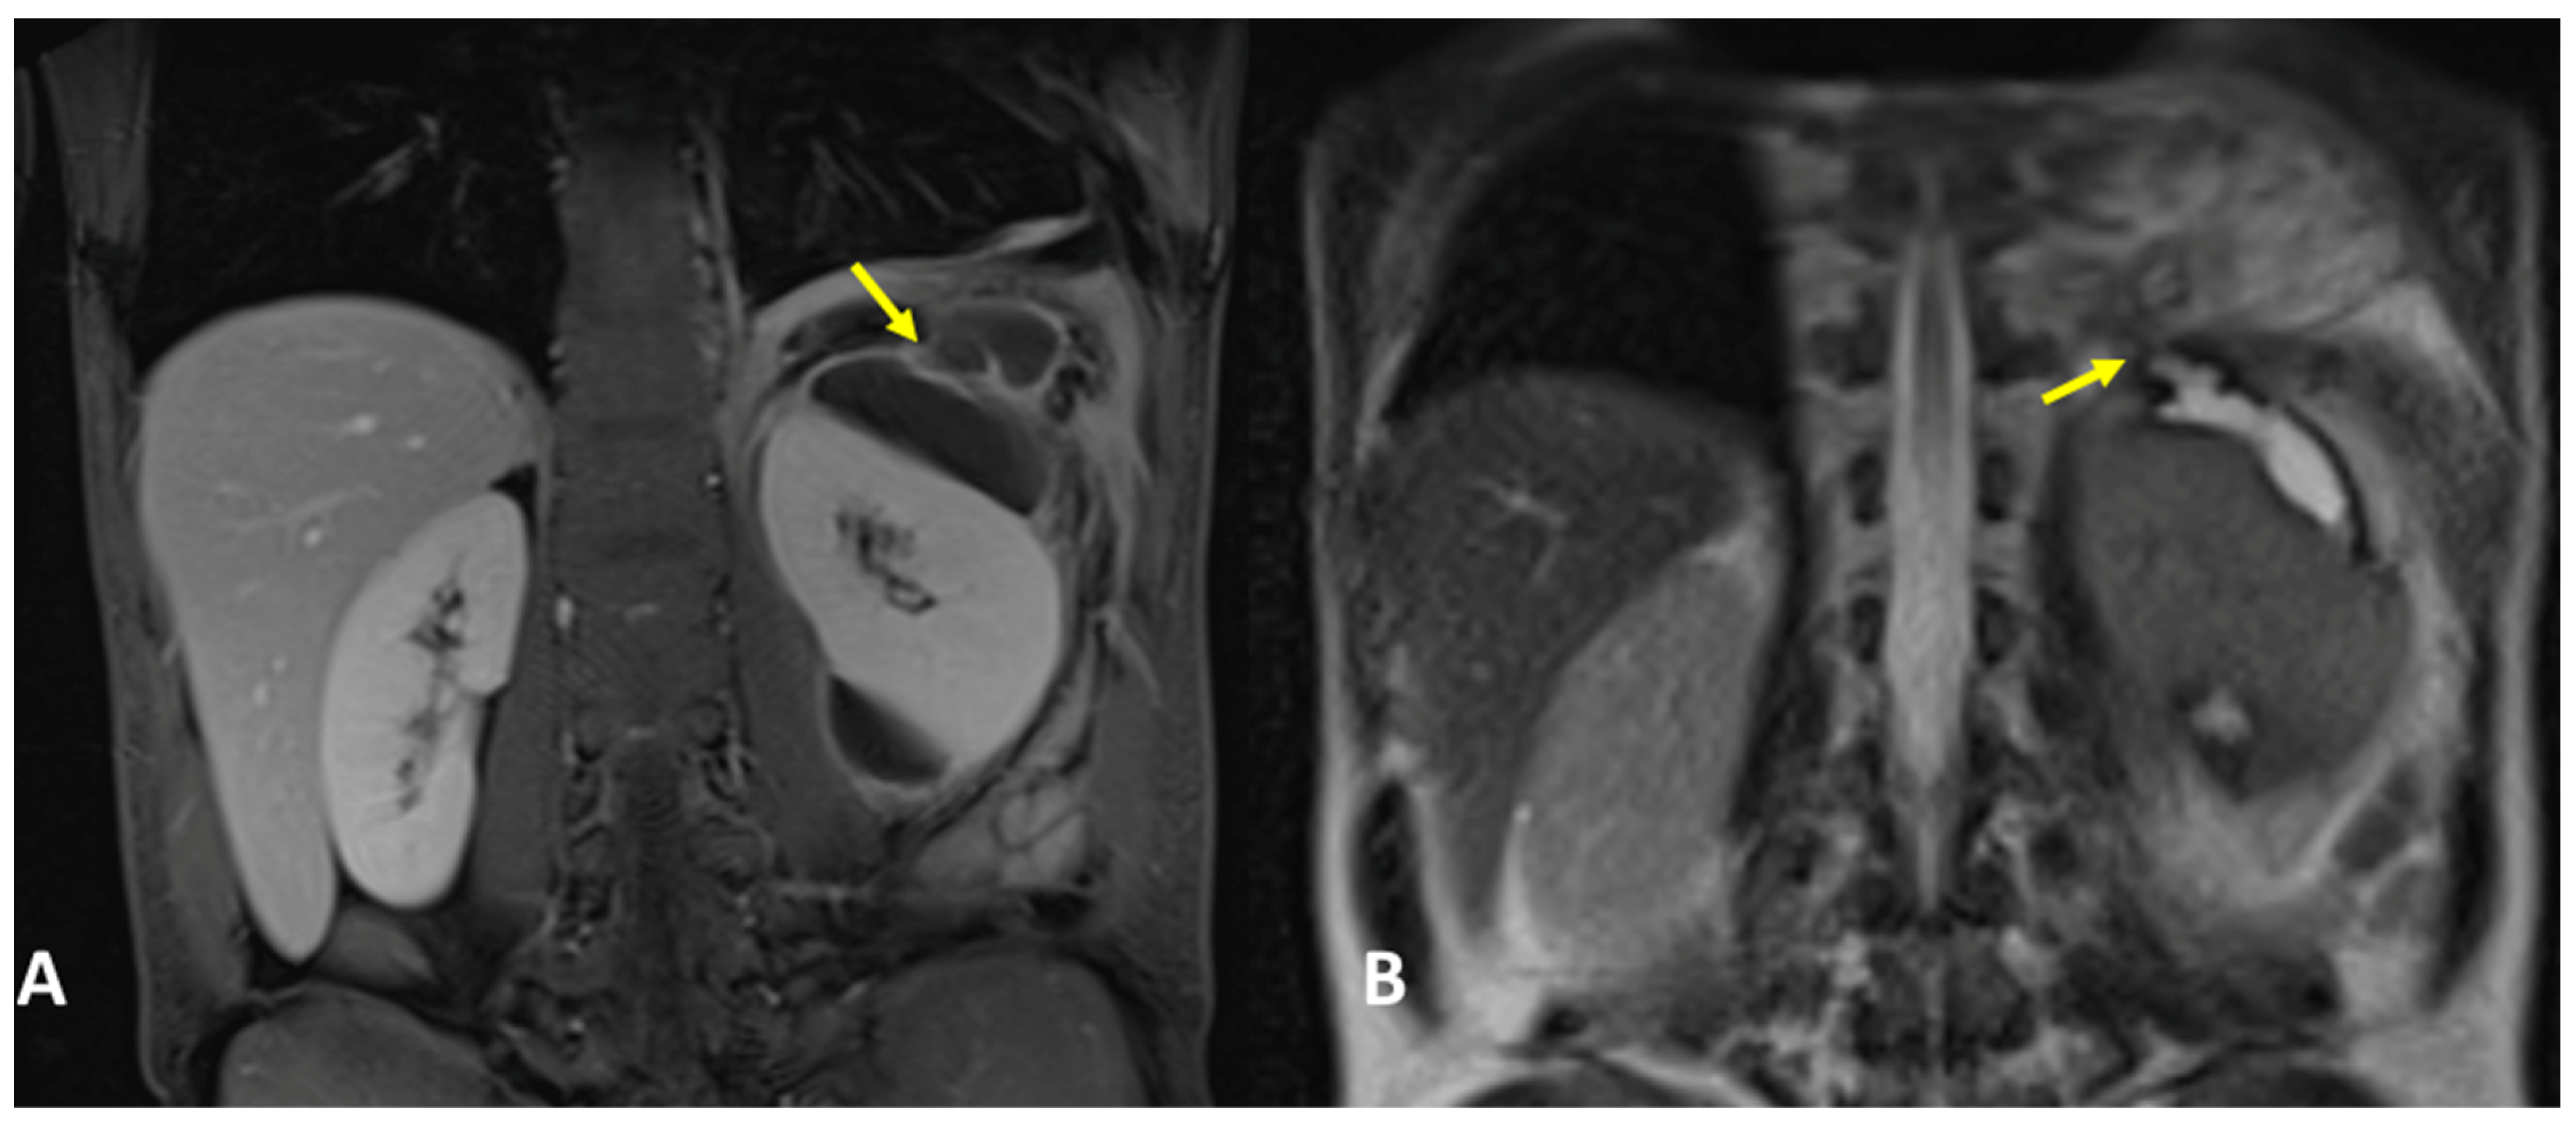

3.4. Case #4: Pancreaticopleural Fistula